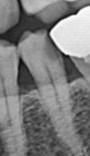

인접면 충치 꼭 신경치료를 해야 하나요? (사진첨부)

사진에 보듯 인접면 충치가 있고 아무런 통증은 없는데 반드시 신경치료후 크라운을 해야 되는 상태인가요?

• 1번 째 사진

엑스레이상으로 저정도 치아 상태라면 신경치료를 해야될것같습니다. 신경치료를 최대한 빠르게 하시는게 좋을것같습니다.

반드시 신경치료를 해야 할 정도는 아닙니다만 거의 간접적으로 치수는 노출된 상태 같습니다.

인레이를 하고자 한다면 치수(신경)에 대해 보호막 물질을 덮어주고 그 다음에 그 위에 인레이를 하면 됩니다

이대로 방치하면 치아가 깨져나가거나, 앞으로 시린 증상이 나타날 가능성이 매우 높습니다.

사진으로 봤을 경우에는 충치가 매우 크게 진행된 것으로 보입니다. 충치를 제거했을 경우 신경에 노출될 가능성이 높으며 노출이 되지 않더라도 치아가 실릴 수 있습니다. 우선 충치를 제거하고 신경치료 여부를 확인하는 것이 좋을 것으로 생각됩니다.